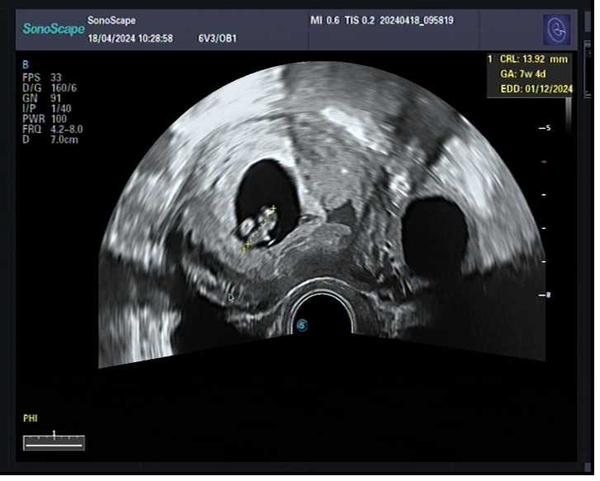

Ahoj asi zvláštní dotaz ale dneska byl i doktor se mnou v údivu. Byla jsem na pohotovosti s tím, že nepravidelně se mi objevují křeče v břiše ale na standardní prohlídce těhu jsem ještě nebyla. Lékař zjistil, že podle utz jsem 5+1 a vidí již srdeční akci ale měřil to několikrát, říkal že mu to nedává smysl a me taky ne, protože kdybych byla 5+1 tak v den početí jsem měla ducha na testu 😂

Ke křečím mi řekl, že mám v děloze nějaký ring sing 😂 můžete mi říct, zda mate někdo podobnou zkušenost? Mimochodem nechráněný styk byl pouze v období ovulace pak už ne 😂 takže početím jsem si jistá 😂

@hanaach Ahoj, tak nevím, proč byl doktor tak "udiven", ale to měření je velmi orientační, protože milimetr sem, milimetr tam, to ti udělá rozdíl i několik dní. Záleží na přesnosti a zkušenosti doktora, stejně tak na použitém přístroji.